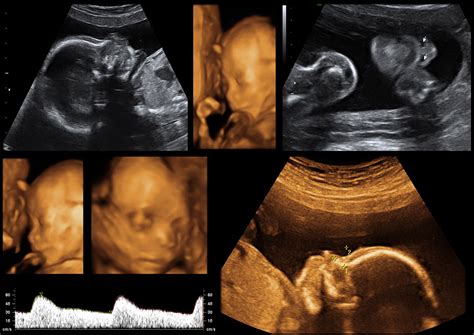

Hey guys, let’s dive into the amazing world of 3D ultrasounds ! If you’re expecting, you’ve probably heard about them, and maybe you’re wondering what makes them so special. Well, imagine going beyond the grainy black-and-white images of traditional ultrasounds. 3D ultrasounds offer a stunning, almost lifelike view of your little one, letting you see their tiny features, their expressions, and even their movements in incredible detail. It’s like getting a sneak peek at your baby before they even arrive, which is pretty darn cool, right? We’re talking about seeing a miniature nose, those adorable little fingers and toes, and maybe even a yawn or a stretch. This technology has revolutionized how expectant parents connect with their unborn child, creating emotional bonds that are truly priceless. Beyond the emotional connection, 3D ultrasounds can also provide valuable medical information. They allow healthcare providers to get a clearer, more comprehensive view of your baby’s anatomy, which can be crucial for detecting certain developmental conditions early on. This means that while you’re marveling at your baby’s cute little face, your doctor is also getting a detailed look at their internal structures. It’s a win-win situation, offering both emotional reassurance and important medical insights. The process itself is similar to a standard ultrasound, using sound waves to create images. However, the advanced technology behind 3D ultrasounds processes these sound waves differently, building up a three-dimensional picture layer by layer. This creates those incredibly realistic images that have captivated so many parents. So, if you’re considering an ultrasound, a 3D ultrasound can offer an unforgettable experience, blending medical accuracy with the sheer joy of seeing your baby in a way you never thought possible. It’s a moment that many parents cherish forever, a tangible memory of their baby’s earliest days.

Now, let’s get a little nerdy, shall we? You might be asking, “How on earth do these 3D ultrasounds create such realistic images?” It’s all thanks to some pretty sophisticated technology. Unlike the 2D ultrasound, which gives you a flat, slice-like image, a 3D ultrasound takes multiple 2D images from different angles. Think of it like taking a whole bunch of snapshots of an object from every side. Then, a powerful computer algorithm stitches all these 2D images together. It’s like a digital puzzle, where the computer pieces everything perfectly to construct a three-dimensional view . This reconstructed image then allows us to see the surface of the baby, giving us that familiar, almost photographic appearance. The technology that makes this possible is called volume imaging . It captures a volume of data, not just a flat plane. This volume data can then be rendered into a 3D image, and importantly, it can also be used to create real-time 4D ultrasounds , which we’ll touch on later! The transducers used in 3D ultrasounds are a bit more advanced, capable of acquiring the necessary data quickly and efficiently. They send out sound waves, and the echoes that bounce back are interpreted by the ultrasound machine. The key difference is how this information is processed and displayed. Instead of just showing one slice, the software compiles a collection of slices to create a cohesive, three-dimensional representation. This process allows for a much more detailed visualization of external features like the baby’s face, limbs, and body contours. It’s this ability to see the baby’s form and features that makes 3D ultrasounds so incredibly compelling for expectant parents. It’s not just about seeing a shape; it’s about recognizing features and building that initial bond. The clearer the image, the more real the baby feels, and that’s the magic that 3D ultrasound technology brings to the table. It’s a remarkable feat of engineering and computer science, all focused on giving parents the most intimate glimpse possible into their baby’s developing world.

Okay, guys, let’s clear up some common confusion: the difference between 3D ultrasounds and 4D ultrasounds . It’s a question many expectant parents have, and the answer is actually pretty simple once you get the hang of it. Think of 3D ultrasound as giving you a static, three-dimensional picture. It’s like a high-resolution photograph of your baby. You can see their features, their form, and their appearance from various angles, but it’s a still image. It captures a moment in time, beautifully rendered in three dimensions. Now, 4D ultrasound takes that 3D image and adds the element of time – hence, the ‘4D’. It’s essentially a 3D ultrasound that’s happening in real-time. So, instead of a still picture, you get a live video feed of your baby’s movements. You can see your baby yawning, stretching, blinking, kicking their legs, or even sucking their thumb, all as it happens! It’s like watching a mini-movie of your little one. The technology is very similar; both use volume imaging to capture data. However, for 4D ultrasounds , the machine captures these 3D volumes consecutively, very rapidly, creating a motion picture. Most elective 3D ultrasound services actually offer 4D imaging as well, because it’s just a different way of rendering the same data that’s captured. When you go for an appointment, you’ll likely experience both. The sonographer will capture the 3D stills for you to take home as photos, and they’ll also record short video clips so you can see your baby in motion. The benefits are similar for both – enhanced bonding, clear visualization – but 4D adds that extra layer of seeing your baby live . It makes the experience even more dynamic and interactive. So, while 3D ultrasound gives you a beautiful, detailed snapshot, 4D ultrasound lets you watch your baby perform their very first actions. Both are incredible technologies that offer a profound connection to your unborn child, but 4D adds that magical dimension of movement and real-time viewing. When choosing a service, most places will bundle these capabilities together, so you get the best of both worlds: stunning 3D photos and engaging 4D video clips.